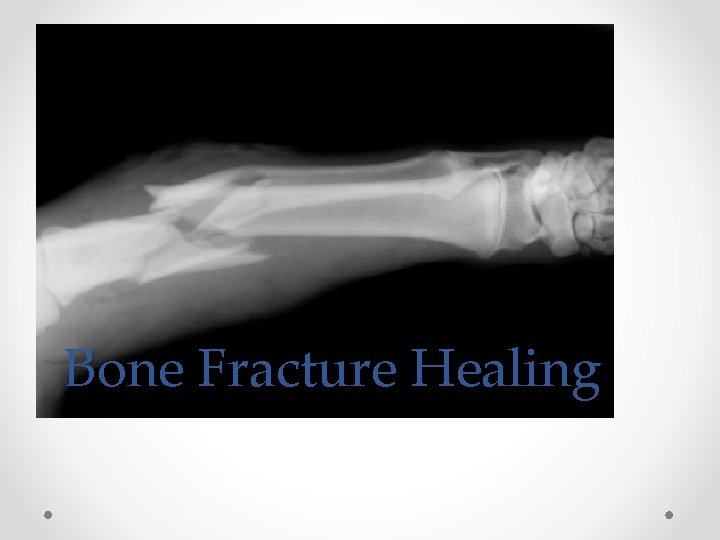

Bone Fracture Healing

Stage I: Acute • Break in bone -> bleeding occurs in area-> osteoclasts (absorb debris) -> osteoblasts (add layers to bone) • Four days

Stage II: Repair • Osteoclasts and osteoblasts continue to rebuild bone. • A fibrous callus forms holding the bone together. • 1 week- 3 weeks

Stage III: Remodeling • The callus is reabsorbed • The callus is replaced with a fibrous matrix